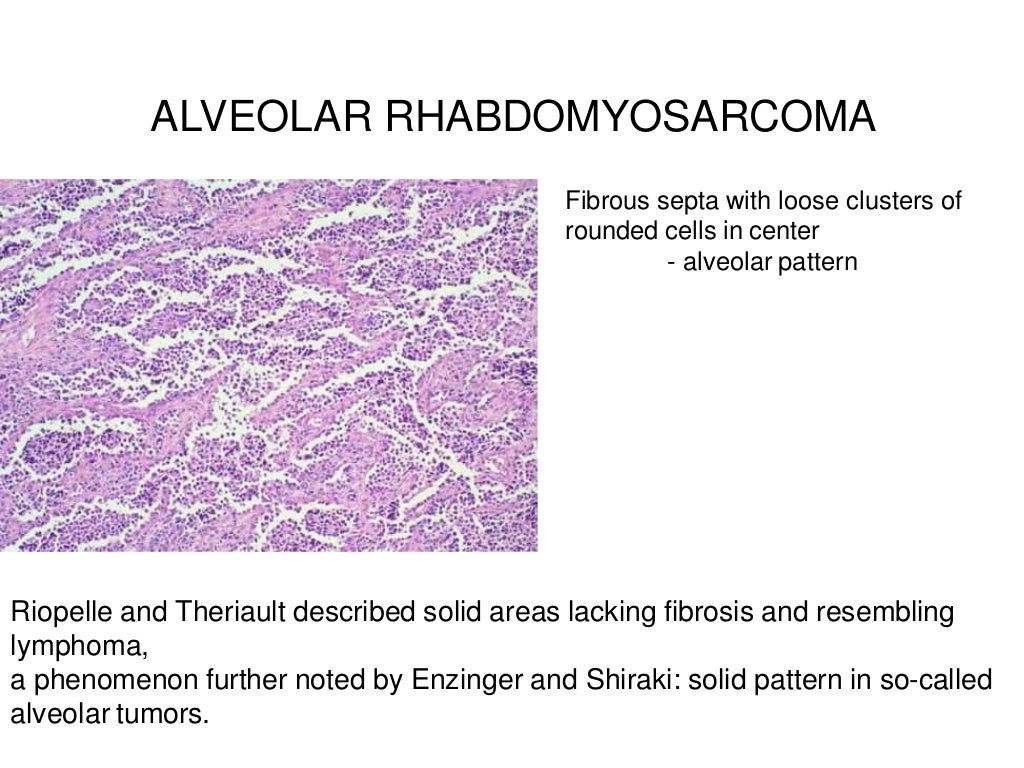

Rhabdomyosarcoma

www.slideshare.net

www.slideshare.net

rhabdomyosarcoma alveolar